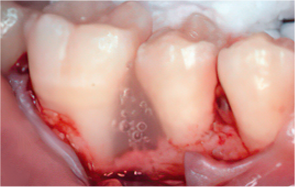

-

STEP 04

Emdogain application

STEP 05

Cleansing